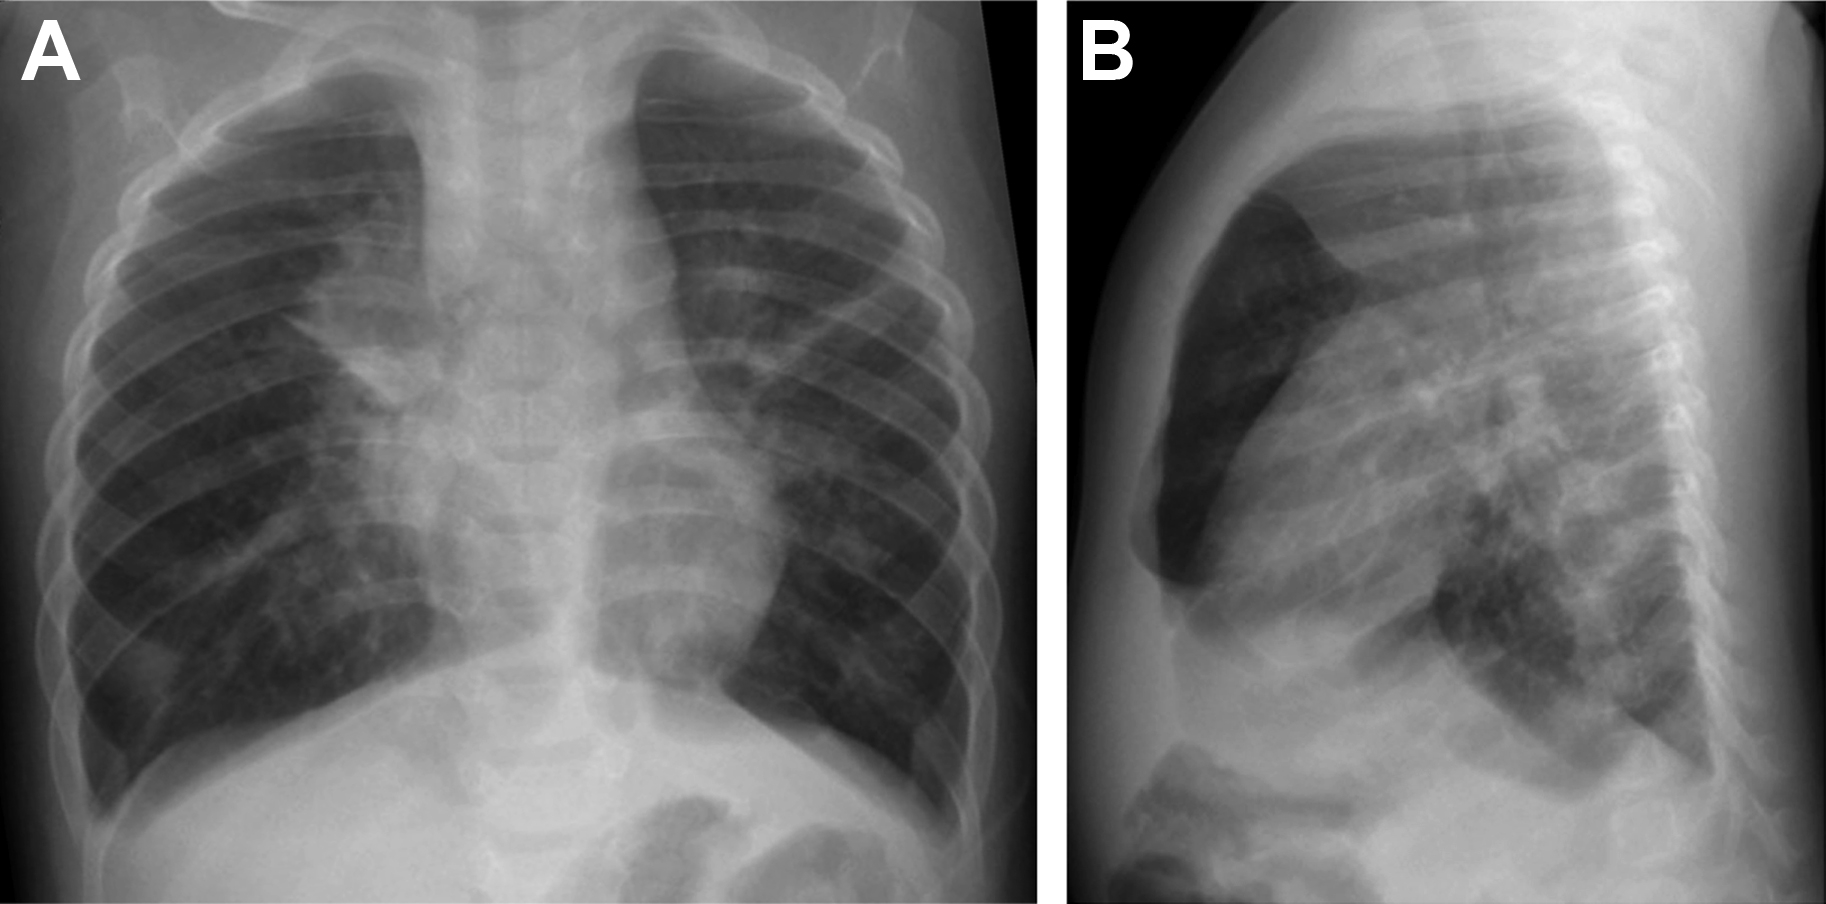

From www.bmj.com

Recurrent chest infection in a 5 year old boy The BMJ Baby Chest Infection High Temperature When to call the doctor. The signs and symptoms depend on what caused the infection and the age of the child. Look out for an abnormally high body temperature, sometimes accompanied by shivering. You should call your child’s doctor if your child: Signs of serious illness in a baby or toddler. Bronchiolitis is a viral chest infection. An upper respiratory. Baby Chest Infection High Temperature.